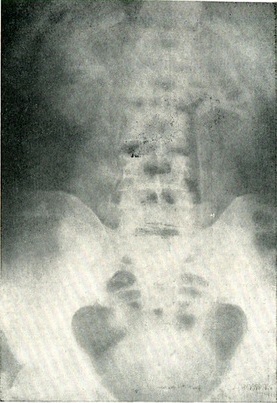

Оглядова рентгенографія. Рентгенологічне обстеження хворого починають з оглядової рентгенографії всій сечової системи. Роблять знімок області нирок, сечоводів і сечового міхура. Крім кісткового скелета, на оглядовому знімку в більшості випадків можна бачити форму і положення нирок, край поперекового м'яза (рис. 37, а). Рентгенографія дає можливість виявити камені нирок, сечоводів, сечового міхура, передміхурової залози, уретри. Оксалати, фосфати і особливо карбонати затримують рентгеновы промені в набагато більшою мірою, ніж навколишні тканини, і тому контуріруются чітко (рис. 37, б), урати, ксантинові, цистинові камені дають слабку тінь або зовсім не видно на оглядових знімках.

Рис. 37. Оглядова рентгенограма області нирок та сечоводів (а), тінь каменя нирки на рентгенограмі (б).